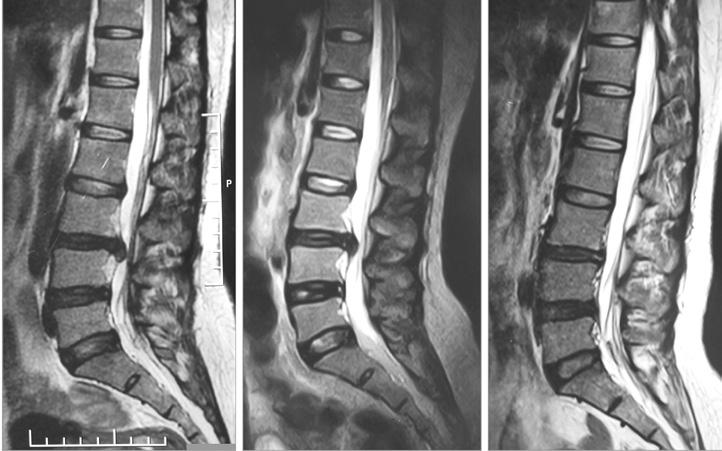

Positive Outcomes in Natural Healing for Complex Spine Conditions

Daniel Bishop, DPT, founder of Complex Spine Therapy in Daphne, is no stranger to chronic pain. After a traumatic car accident in high school led to a five-level spinal fusion and 18 months of rehabilitation, he experienced firsthand the challenges and triumphs of healing. That life-altering experience shaped his future—and his life’s work.

Today, Dr. Bishop brings more than 23 years of expertise in spinal health to his patients. A sixth-generation Baldwin County native, he has treated over 20,000 cases of serious spinal injury in the region and is known for his compassionate, tenacious approach to care. “I take every patient’s outcome personally,” he says. “Most people don’t realize that their spine can heal. It just needs the right conditions.”

body is capable of healing—even regenerating—when we support it properly.”

Combining advanced physical therapy with advanced dry needling, high intensity light therapy, shockwave therapy, PEMF, Advanced Postural Biomechanical Correction (APBC), postural alignment and individualized nutrition and lifestyle coaching, Bishop and his team help patients reduce pain and regain mobility. In many cases, complete resolution of symptoms—even with those with severe disc issues— happens in just a few weeks. He states, “I've had remarkable results with this problem for over 20 years in a market that is failing miserably at longterm solving this problem.”

in sequestered or extruded discs, is a documented phenomenon. With a comprehensive, conservative care plan, patients can often avoid surgery entirely.

Bishop is seeing remarkable outcomes in patients who were told they needed surgery, injections or lifelong medication. His clinic specializes in natural, non-surgical care for complex spine disorders, particularly degenerative disc disease and lumbar disc herniations—conditions often believed to be irreversible. “We’ve been led to believe that once the spine starts to degenerate, there’s no going back,” he explains. “But the

“Degenerative disc disease is often caused by poor posture, inactivity and strain from modern lifestyles,” he says. “This leads to inflammation, loss of disc height, and eventually nerve compression and spinal stenosis. But these tissues—especially the posterior disc, made of Type I collagen— are capable of healing with proper blood flow, nutrition and movement.”

Research confirms that spontaneous healing of spinal disc herniations, particularly

“We’re seeing near 100 percent success stopping pain almost immediately—without medication or surgery—using a powerful blend of advanced dry needling, high intensity light therapy, shockwave therapy, PEMF, Advanced Postural Biomechanical Correction (APBC) and lifestyle modifications.” -Dr. Daniel Bishop

Bishop is concerned about the growing trend of unnecessary spine surgeries and overuse of medications like opioids and steroids. “People in pain are vulnerable,” he says. “They’re desperate for relief, and too often they’re not told that there are other options. Conservative regenerative care should always be the first step.”

His approach reflects a deep belief in the body’s ability to heal—and in the importance of educating patients. “Only you can heal your disc problem with education and regenerative healing efforts to regenerate your disc back to normal,” he says. “But you don’t have to do it alone. With the right support, healing is not only possible—it’s expected.”